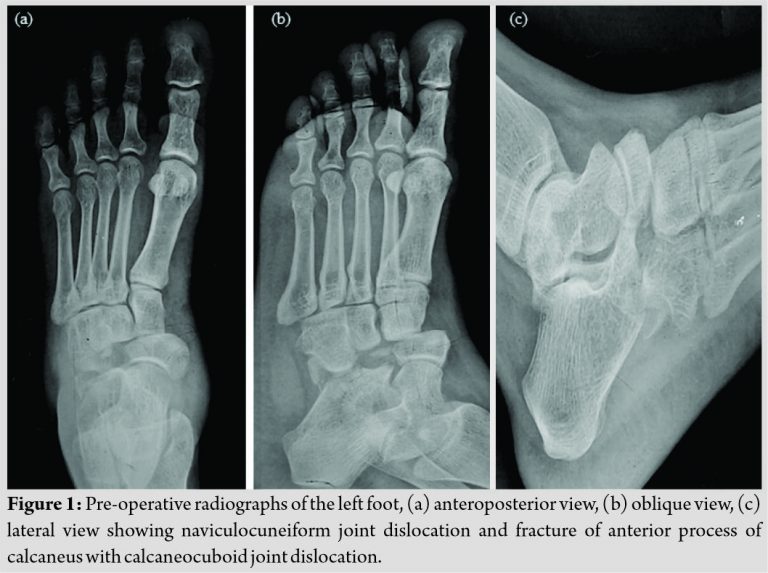

A 30-year-old female (weight 65 kg and height 158 cm) came to our emergency department with injury to the left foot, due to fall from the stool of height approximately 2 feet. She lost her balance while arranging things in overhead cupboards when she was standing on a stool with heels elevated and landed on the floor with plantar flexion at ankle joint and abduction at midfoot. She presented to us immediately after trauma with pain and swelling over the midfoot region without any external wounds. On clinical examination, there was severe tenderness over mid-foot, and abnormal bony prominence was present over the dorsomedial aspect of the left foot, without any distal neurovascular deficit. Midfoot joint movements were severely restricted, making the patient unable to walk. The radiographs of the left foot were done in the form of anteroposterior, lateral, and obliques views. Radiographs revealed naviculocuneiform joint dislocation and fracture of anterior process of the calcaneus with calcaneocuboid joint dislocation (Fig. 1).